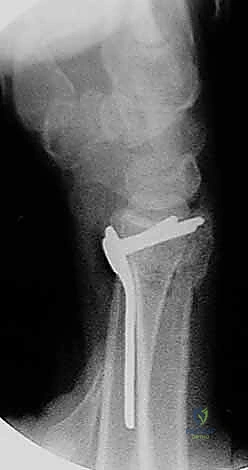

4. وضع الصفيحة والتثبيت المؤقت

يتم اختيار صفيحة تيتانيوم مصممة تشريحياً لتلائم انحناء الكعبرة. توضع الصفيحة على العظم وتُثبت مؤقتاً بأسلاك معدنية دقيقة (K-wires).

5. حفر العظم ووضع المسامير

يتم حفر ثقوب في العظم عبر فتحات الصفيحة، ثم تُقاس المسافات بدقة لإدخال مسامير القفل (Locking Screws) في الجزء البعيد (قرب المفصل) ومسامير قشرية في الجزء القريب (في ساق العظم).

6. الفحص النهائي والإغلاق

يتم إجراء فحص أخير بالأشعة للتأكد من المحاذاة المثالية للكسر وأطوال المسامير (لضمان عدم بروزها واحتكاكها بالأوتار الخلفية). بعد ذلك، يتم خياطة الأنسجة والجلد بخيوط تجميلية ووضع ضمادة معقمة.